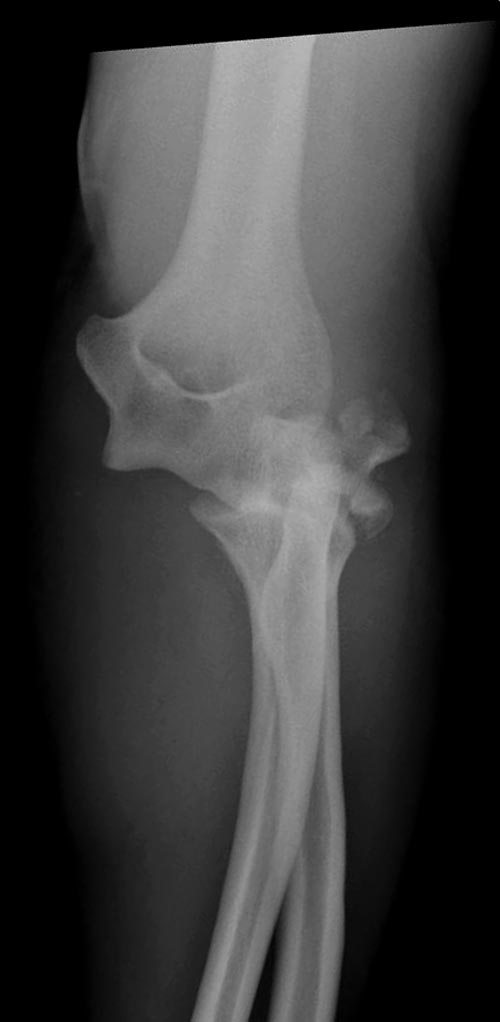

Судя по 3-Д КТ, перелом - много оскольчатый, но без смещения.

Один снимок всего? Может КТ-срезы какие-нибудь есть, R-снимки без гипса фас/профиль? По этому снимку вроде бы и нет вдавленного перелома. Суставная поверхность расколота - это да, но импрессии не увидел. Мы бы попытались сохранить головку.

Синтезировать, или вообще не трогать. А 3D картинки дают мало информации. Лучше представляйте срезы в 3-х плоскостях.

На представленных снимках есть смещение суставной поверхности. Принцип лечения внутрисуставных переломов - восстановление суставной поверхности. У нас есть опыт восстановления таких переломов микровинтами. Удачи!

Для выработки показаний достаточным бывают стандартные снимки, но иногда требуется косая рентгенограмма по Coyle. И для подтверждения смещений и оценки внутрисуставных фрагментов рекомендуется КТ, а 3D снимки показывают только поверхность, т.е. получается общая картина. МРТ дает возможность оценить состоянии связок.